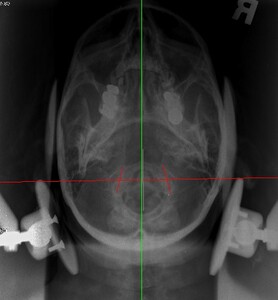

Upper cervical orthogonal based x-rays to measure for significant upper cervical misalignment.17,21,22 (Figure 2 a,b,c)

These films are used to determine atlas misalignment, develop a correction strategy and confirm an appropriate correction has been made.

The x ray measurements have been charted to show changes in Atlas laterality, Atlas rotation and degrees of change in angular rotation (measurement in degrees that the cervical spine is off the vertical axis). (Table 3).